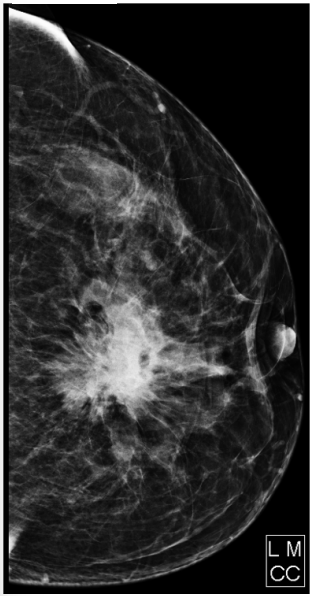

Paciente do sexo feminino, 65 anos de idade, comparece ao serviço para realização de mamografia, queixando-se de massa palpável em mama esquerda e retração de papila. Com relação ao exame abaixo e ao sistema de classificação BI-RADS, assinale a alternativa CORRETA.

Figura 3 – Mamografia.

Fonte: CPCON.